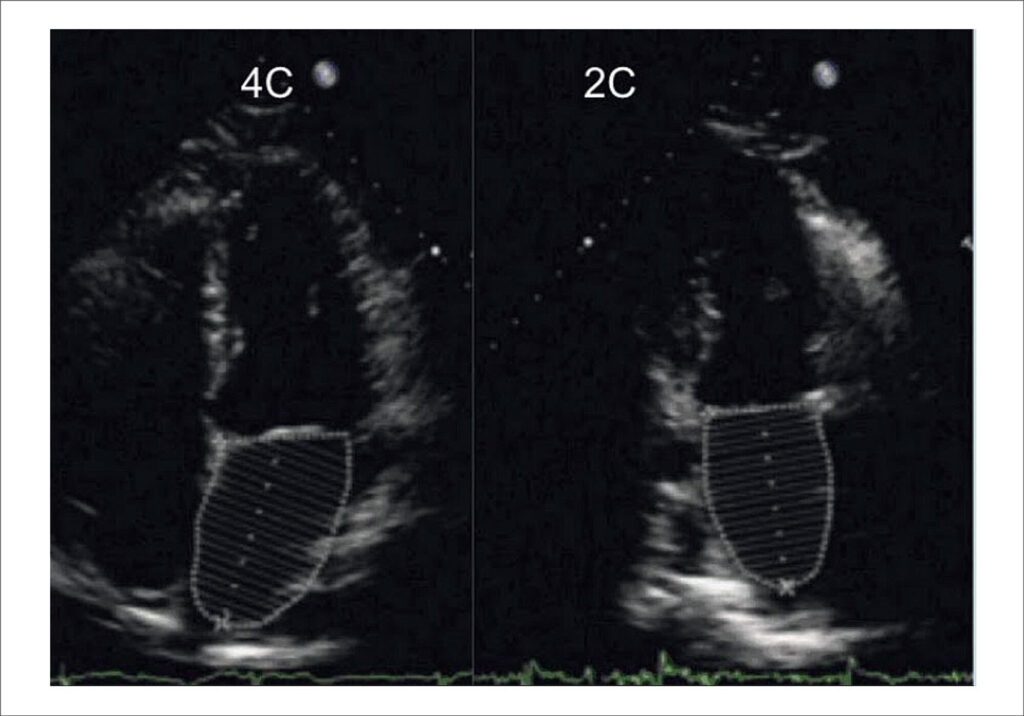

Diante disso, o reconhecimento precoce dos marcadores da miocardiopatia falcêmica, através dos parâmetros ecocardiográficos (Figura Central), é fundamental para a conduta adequada da condição cardiovascular destes doentes.

Essa revisão abordará de forma objetiva e didática o uso da ecocardiografia em pacientes pediátricos com DF, mostrando as principais particularidades nesta doença e a importância do acompanhamento regular.